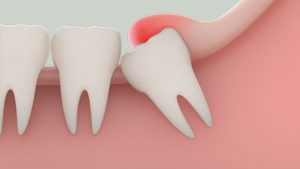

Khi không có đủ chỗ để mọc thì việc răng khôn mọc lệch sẽ gây đau hoặc gây khó chịu. Nếu như chỉ có một phần trồi lên và bị hư hại thì nhiều răng khác lân cận cũng sẽ bị hư hại khi nó không được làm vệ sinh sạch sẽ.

Răng khôn mọc lệch còn có khả năng chen chúc và xô đẩy sang các răng kế cạnh gây đau đớn. Nguy hiểm hơn là răng khôn mọc ngầm ở dưới hoặc được phần lợi bọc kín rồi đâm ngang qua chiếc răng số 7 bên cạnh. Hậu quả của việc răng khôn mọc lệch là: gây nhiễm trùng, khít hàm, sưng, đau nhức… Vì thế, răng khôn mọc lệch thường được bác sĩ chỉ định nhổ bỏ để tránh tình trạng nhiễm trùng, tiêu xương ở ổ răng bên cạnh, hư hại răng bên cạnh và tạo nang răng xương hàm.